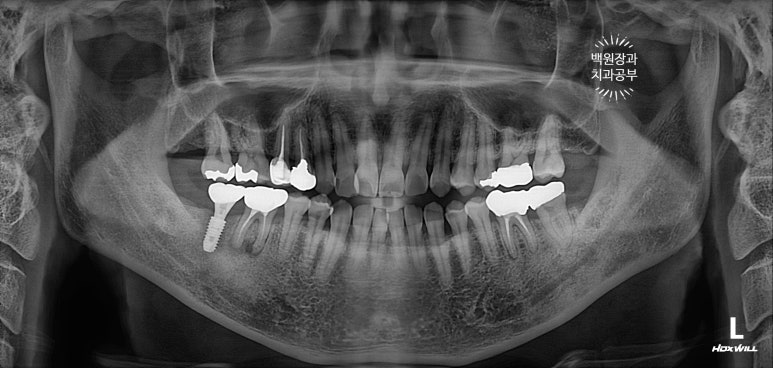

치과용 파노라마 엑스레이를 보니 오른쪽 아래 두번째 큰어금니와 왼쪽 아래 사랑니가 머리가 부러져 있네요.

그 중 오른쪽 아래 어금니는 신경치료를 하셨던 이빨인데, 이차 충치가 심해서 부러진 모양입니다.

그리하여 수술 후 치과용 파노라마 사진입니다.

임플란트 위치가 아주 듬직하니 마음에 드네요!!

임플란트 완성 후 치과용 파노라마 사진입니다.

임플란트가 이상적인 모양으로 예쁘게 제작된 것을 보실 수 있을거에요!